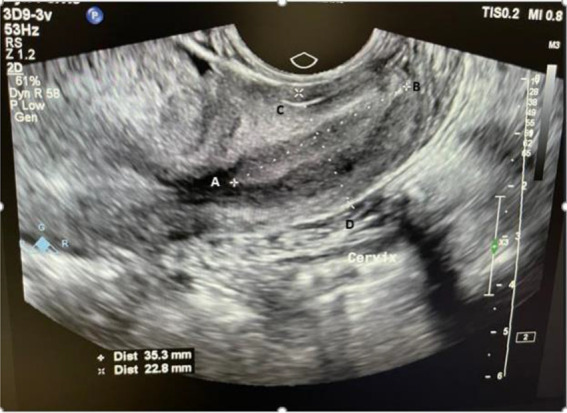

Methods: In this case-control study, the case group consisted of nulliparous women with endometriosis, while the control group comprised nulliparous women without endometriosis. A total of 42 individuals were included in each group. Cervical length was measured using transvaginal ultrasound from the external os to the internal os. The patients in the case group underwent laparoscopy to confirm the diagnosis. Pearson chi-square test and Fisher's exact test were employed to compare categorical variables with a p<0.05 considered statistically significant.

Results: In both groups, there were no notable variations in any of the demographic characteristics. However, the severity of dysmenorrhea was significantly different between the two groups (p=0.01). The average diameter of the mediolateral cervix (29.48±6.2 and 27.14±3.8) was statistically significant between the patient group and control group, respectively (p=0.04). The mediolateral width may have a positive predictive effect on the presence of endometriosis, while cervical length appears to have a protective effect against endometriosis.

Conclusion: Demographic data do not predict endometriosis. This study suggests that mediolateral width in transvaginal sonography can serve as a minimally invasive diagnostic tool for endometriosis, showing correlation with endometriosis symptoms like dysmenorrhea and dyspareunia.